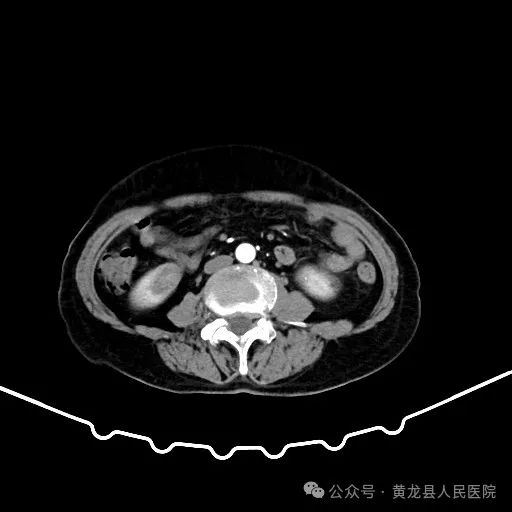

患者男性,70岁,因“发现右肾肿物1年余”收住于我院外科,经查体及相关检查后诊断为:右肾肿瘤。为尽早解除患者疾病困扰,方继荣主任迅速组织泌尿外科、手麻科、普外科等多学科进行会诊,对患者的病情进行了全面而深入的评估。最终确定详细周密手术方案,将患者病情及治疗方法告知患者及家属征得同意后,由我院泌尿外科刘涛主治医师实施手术。

双肾增强CT